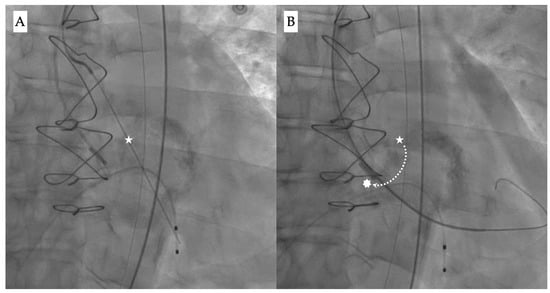

The “commissural drop” wiring technique may allow for a safer crossing during the procedure [,]. It describes the movement of the pre-shaped super stiff wire (e.g., Safari, Boston Scientific) from the center of the valve into the inter-commissural space between the non-coronary and right cusps, thus leaning towards the outer curvature of the aorta (Figure 3A,B). This is usually a sign of correct crossing through the central valvular orifice and provides a visual clue to confirm a safe position before proceeding.

Figure 3.

Fluoroscopy images showing (A) the initial position of the wire during valve crossing (white star), and (B) guidewire drop down (dotted line) from the center position into the inter-commissural space between the right and non-coronary cusp (white asterisk).